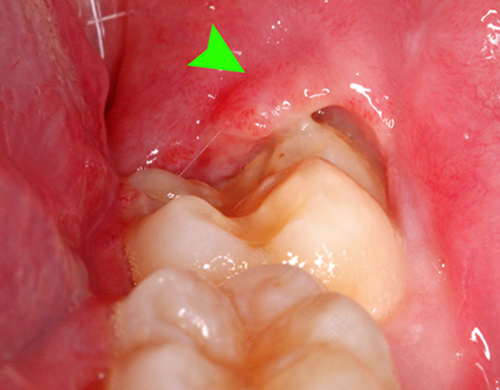

当人们的牙齿生病以后,都会去往专门的口腔医院接受专业的牙医治疗。当病情严重时,牙医会建议进行拔掉牙齿的手术,尤其是智齿,如果不及时拔掉,会让口腔滋生出各种细菌,那么,拔下面智齿疼几天能好?

一般情况下,在进行拔智齿手术后,牙医会在拔掉智齿的部位敷上消炎止痛类的药物。手术时会使用的麻药,当其麻醉效果消失后,伤口部位会肿痛几天,大概一周左右就会痊愈,所以在术后尽量避免吃辛辣刺激的食物,饮食宜清淡为主,最好吃半流体食物。